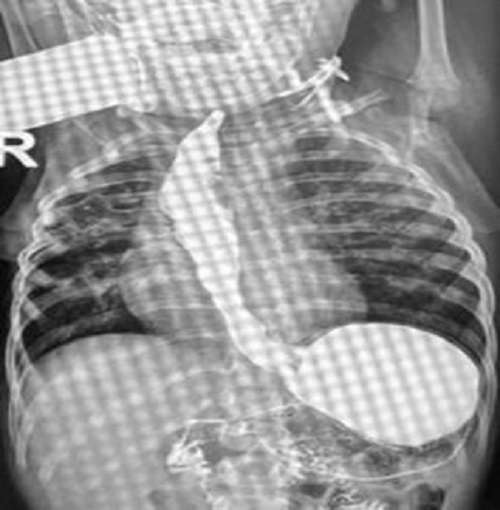

The child is on regular follow-ups for 2 years. The contrast study shows a patent but dysmorphic esophagus (Fig. 3). However, he is accepting oral feeds well. His growth parameters are in the 30-50 percentile for age.

Follow-up contrast study after 2 years.